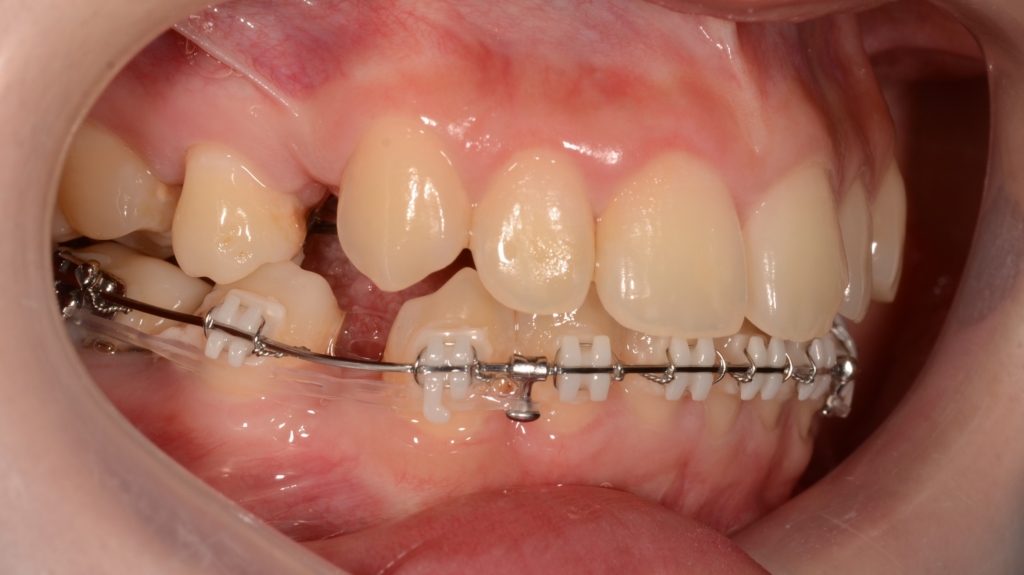

マルチブラケットシステム(ハーフリンガルtype)で矯正を開始。

アンカースクリューを2本使用

順当にステップが進んで、前歯を奥へ引っ込めるためのアンカースクリューを上顎の口蓋中央部分に植立します。

上下とも前歯を奥へ出来るだけたくさん引っ込めるように治療を進めます。